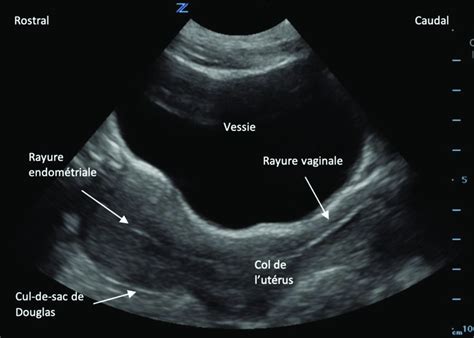

L'échographie, en particulier l'échographie transrectale, est devenue un outil indispensable dans le diagnostic gynécologique de la jument. Le suivi gynécologique par échographie régulière de l'appareil génital par voie transrectale est le quotidien de tout vétérinaire équin ayant une clientèle typée élevage. L'échographie utérine de début de saison est l'occasion de faire le bilan de l'état de santé de l'environnement utérin, permettant de détecter des signes d'endométrite chronique, la présence de kystes, de lacunes, d'accumulations liquidiennes, et d'évaluer la tonicité et la contractilité utérines.

- Palpation rectale et échographie transrectale : Évaluation de la taille, de la forme et du tonus du col utérin, de l'utérus et des ovaires. L'échographie permet de détecter l'accumulation de liquide, les kystes utérins, et d'évaluer la présence de follicules ou d'anomalies ovariennes.